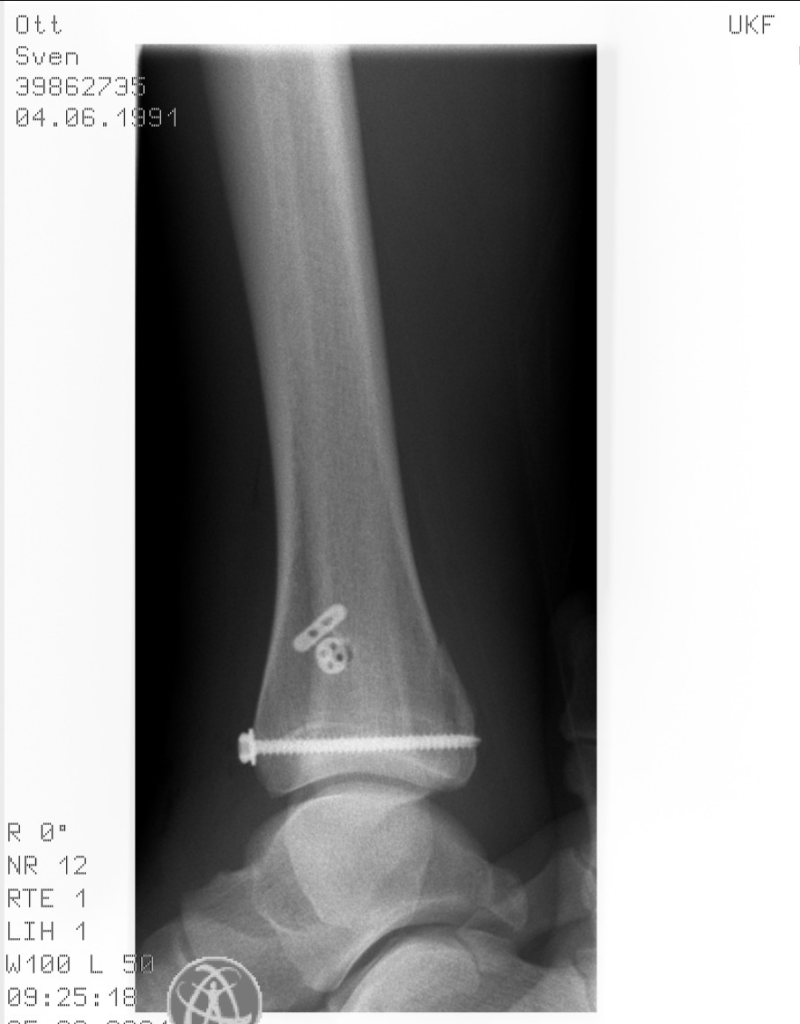

Eine kleine Unachtsamkeit, eine etwas zu gewagte Forschheit bremst den haltlosen Auftrieb der letzten Monate in die 2,40m Deckenhöhe einer kleinen möblierten Wohnung im Freiburger Westen, ein Zimmer, Küche, Bad, ein Balkon mit zwei Monobloc-Plastikstühlen. Einer „Maisonneuve-Fraktur“ — also ein ausgerissenes Volkmann-Dreieck am Schienbein, eine gerissene Syndesmose und ein gebrochenes Wadenbein — folgt eine Operation, eine sechswöchige Ruhigstellung und schließlich eine insgesamt dreimonatige Kletterpause.